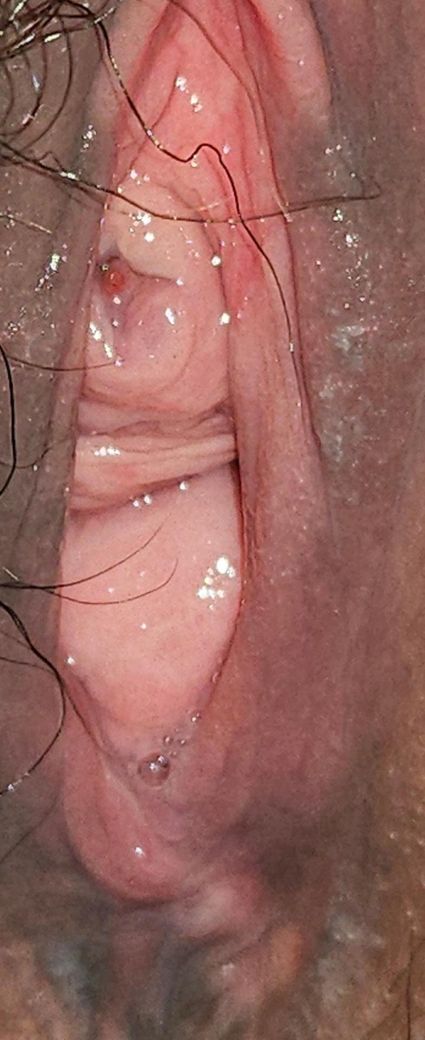

요도구가 이상해요ㅠㅠ 제발좀 알려주세요ㅠㅠ왜 이런걸까요

요도구에 뾰루지 같은게 있다는걸

처음에 알게된건 외음부에 뭐가 나서 사진찍어서

보게 되었는데요

(첫번째사진이 처음 발견햇을 당시에요

그냥 뭐가 났나 싶었어요)

그러고 갑자기 생각나서 한3주후에

그러고 나서 진료본날 집에서 찍은 사진이 이상해서요

뾰루지는 없어지고 전체적으로 점막이 붓고 빨갛고 구멍이 없어졌어요ㅠㅠ대체 왜그런걸까요?..

(소변볼때나 평상시 아프거나 하지도 않고 혈뇨라던지 다른증상도 없어요..)

• 1번 째 사진

• 2번 째 사진

• 3번 째 사진

말씀하신 경과와 사진 설명을 종합하면 요도 카룬클(urethral caruncle) 가능성이 가장 높아 보입니다. 40대 이후 여성에서 흔하고, 요도 입구 점막이 국소적으로 돌출되었다가 자극이나 촬영 각도, 혈류 변화로 전체 점막이 붓고 붉어 보일 수 있습니다. 처음엔 뾰루지처럼 보였다가 이후에 구멍이 안 보일 정도로 부어 보이는 양상도 설명됩니다. 통증, 배뇨통, 혈뇨가 없는 점 역시 전형적입니다.

요도 카룬클은 악성인 경우가 드물고, 대부분 호르몬 변화나 점막 위축, 마찰로 생기는 양성 병변입니다. 크기 변화가 없고 출혈이나 통증이 없다면 경과 관찰만 하기도 합니다. 다만 점막이 계속 심하게 붓거나 색이 진해지거나 쉽게 출혈하면 국소 스테로이드 연고나 에스트로겐 연고 치료를 고려합니다. 아주 드물게 모양이 비전형적일 경우 조직검사를 하기도 합니다.

지금 상태에서 응급 소견은 없어 보이며, 2차 병원 진료를 기다리셔도 의학적으로 위험해 보이진 않습니다. 그 전까지는 잦은 확인이나 강한 세정, 사진 촬영으로 벌리는 행동은 피하고, 좌욕 정도만 가볍게 하시는 것이 좋습니다. 불안이 크시겠지만 현재 정보만으로는 급성 질환이나 암을 강하게 의심할 근거는 낮습니다. (보통 수술 가능한 비뇨기과에서 봅니다.)